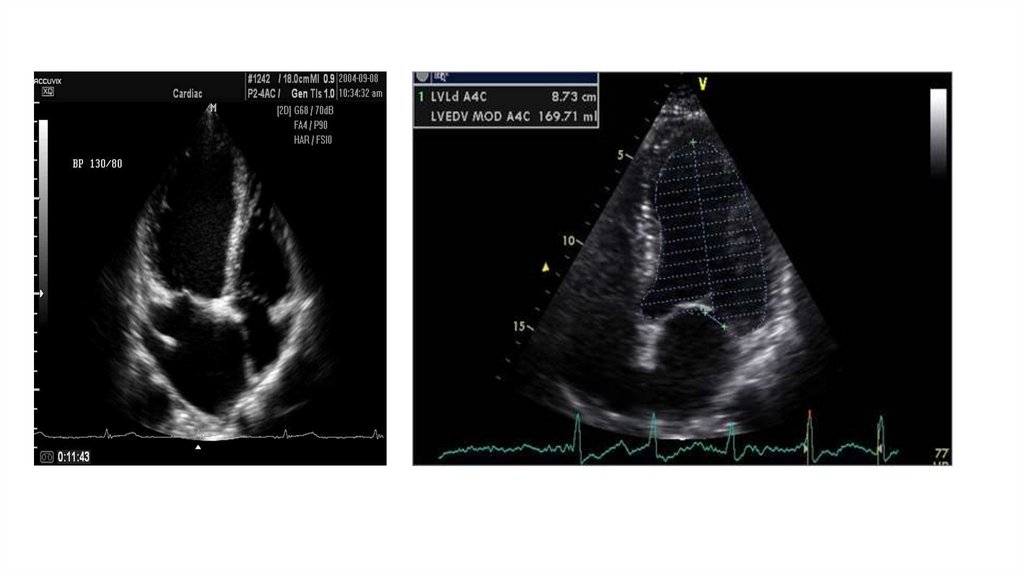

ЛЕЧЕНИЕ АТЕРОСКЛЕРОЗА

17. ЭХО-кардиография

• ЭХО-кардиография – метод, основанный на ЭХОлокации.

• ЭХО – КГ позволяет видеть и записать размеры

полостей сердца, состояние клапанов, наличие

ревматических гранулем на клапанах и т.д.

• ЭХО – КГ оценивает сократительную способность

сердца (сердечный выброс)